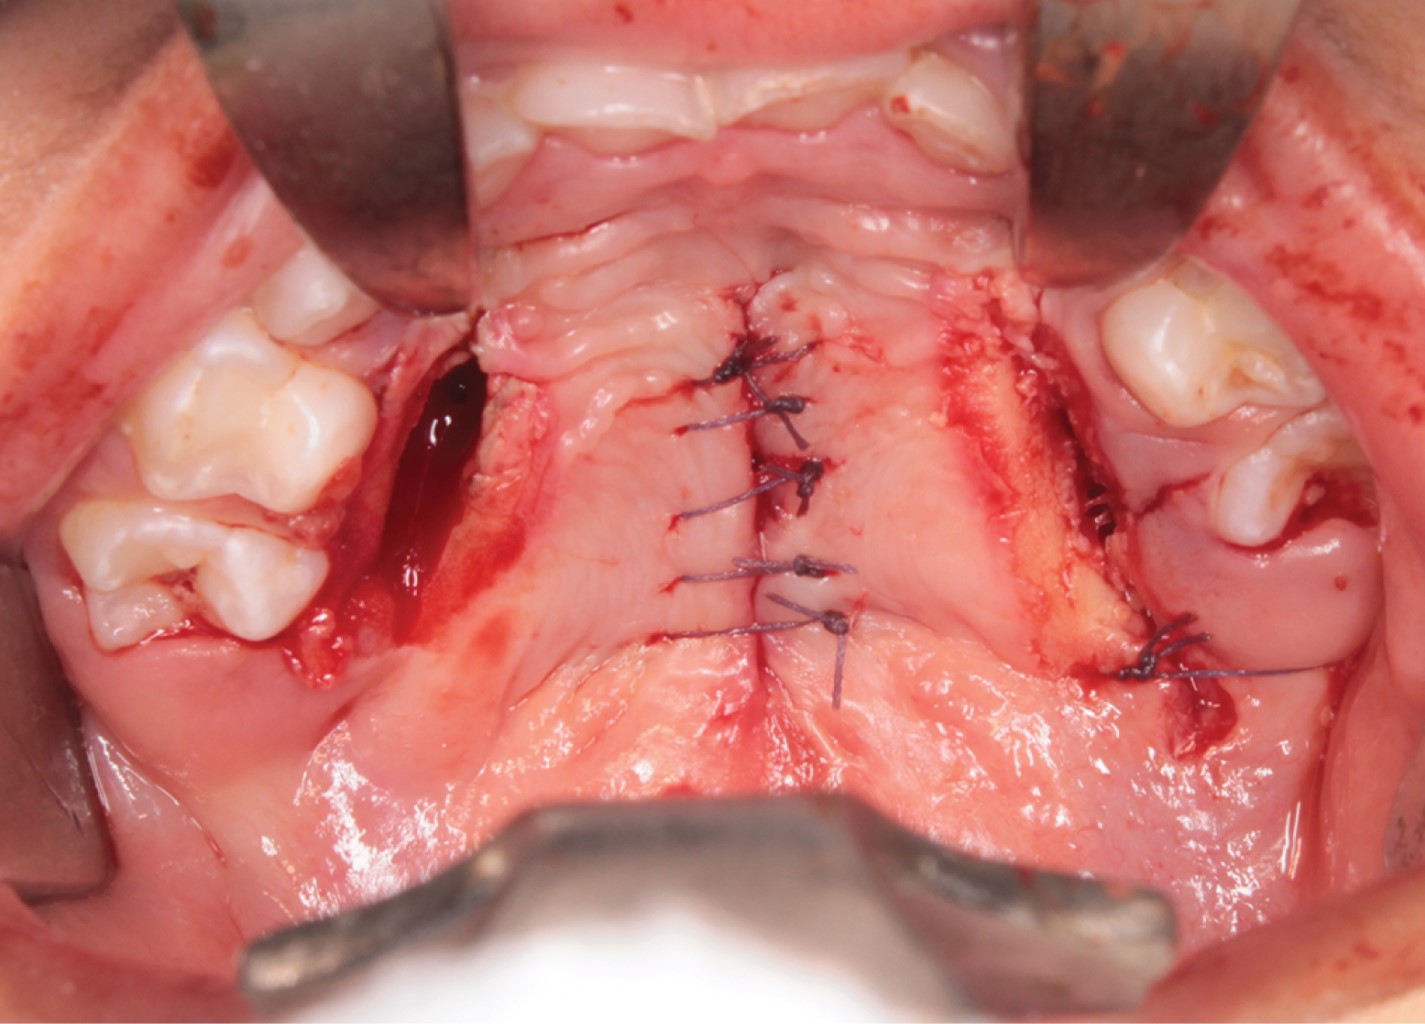

Se presenta el caso de un paciente pediátrico masculino, quien fue llevado al Servicio de Cirugía Maxilofacial del Centro de alta Especialidad "Dr. Rafael Lucio" a la edad de un año cinco meses. Fue valorado y diagnosticado con fisura de paladar secundario clasificación II de Veau (Figura 1), por lo que se le realizó palatoplastia mediante técnica de veloplastia intravelar bajo anestesia general balanceada; la cirugía se llevó a cabo sin complicaciones ni eventualidades (Figura 2). El paciente fue dado de alta; acudió a controles posquirúrgicos a la semana, al mes y a los seis meses; durante este seguimiento fue posible observar la presencia de una fístula palatina Pittsburgh IV +, Cohen II, la cual provocaba paso de líquidos desde la cavidad oral a la nasal (Figura 3).

Después de seis meses de la palatoplastia primaria, se decidió realizar cierre de fístula. Con el paciente bajo anestesia general balanceada, se efectuaron incisiones en los bordes de la fístula, separando las capas nasal y oral, cerrando en dos planos, utilizando un colgajo de mucosa oral invertida para la capa nasal y reclutando tejidos locales para un colgajo mucoperióstico utilizado para el cierre de la capa oral, apoyado de incisiones relajantes. El procedimiento se llevó a cabo sin complicaciones ni eventualidades (Figuras 4 y 5). El paciente fue dado de alta; acudió a controles postoperatorios después de una semana, un mes y seis meses, cursando con una cicatrización adecuada. Actualmente cuenta con dos años de evolución, se encuentra asintomático y sin datos de recidiva de fístula palatina (Figura 6).

Figura 3

Figura 4